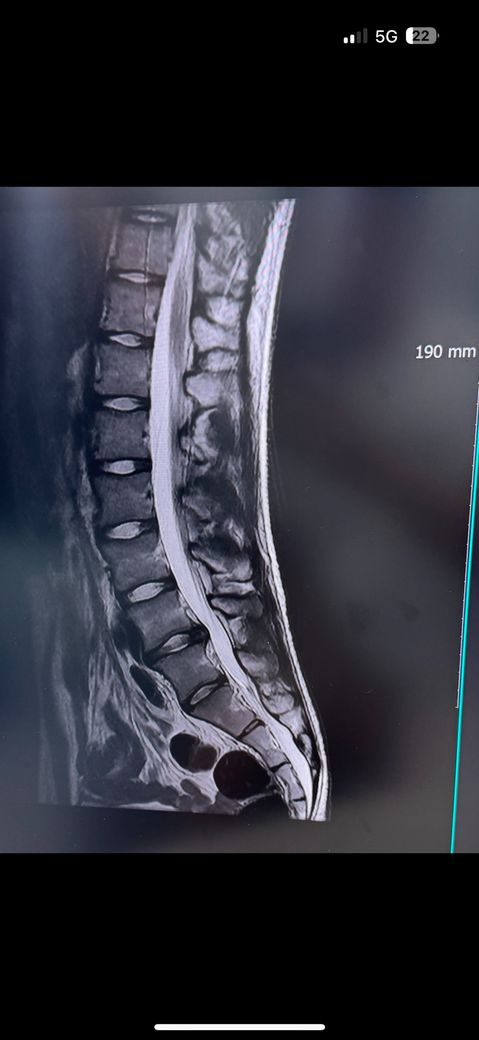

허리디스크 돌출인데놀이공원롤러코스터 타도 될가요오사카 유니버셜스튜디오를 가는데 롤러코스터 타도될가요? 허리에 무리많이가나요?작년 11-12월달부터 허리아파서 이번년도3월에 mri찍었더니 허리디스크 돌출판정 받고 신경주사치려도 4-5번 받았어요 약먹으면 좀 괜찮아지는데 안먹으면 다시 아파요 밑에 mri사진있어요

• 1번 째 사진